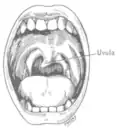

Wanneer de kokhalsreflex aan één kant van het lichaam ontbreekt, kan dit duiden op een laesie aan N. IX, of mogelijk aan N. X.[13]

Schade aan de zenuw op een laag motorneuronniveau kan leiden tot groefvorming in de tong, of atrofie van de tongspieren. Van de groeven in de tong wordt gezegd dat het lijkt op een 'zak wormen'. Hogere beschadigde motorneuronen geven geen atrofie of groefvorming, maar alleen zwakte in de bijbehorende spieren.[3] Als de zenuw beschadigd raakt, kan dit leiden tot beperking van de beweging van de tong aan één kant. Wanneer de tong wordt uitgestoken, wijkt deze af naar de beschadigde, zwakkere kant (zie afbeelding rechts).[3]